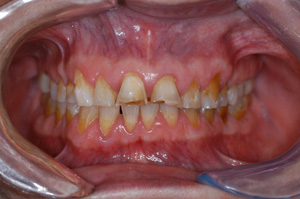

Clinical Cases